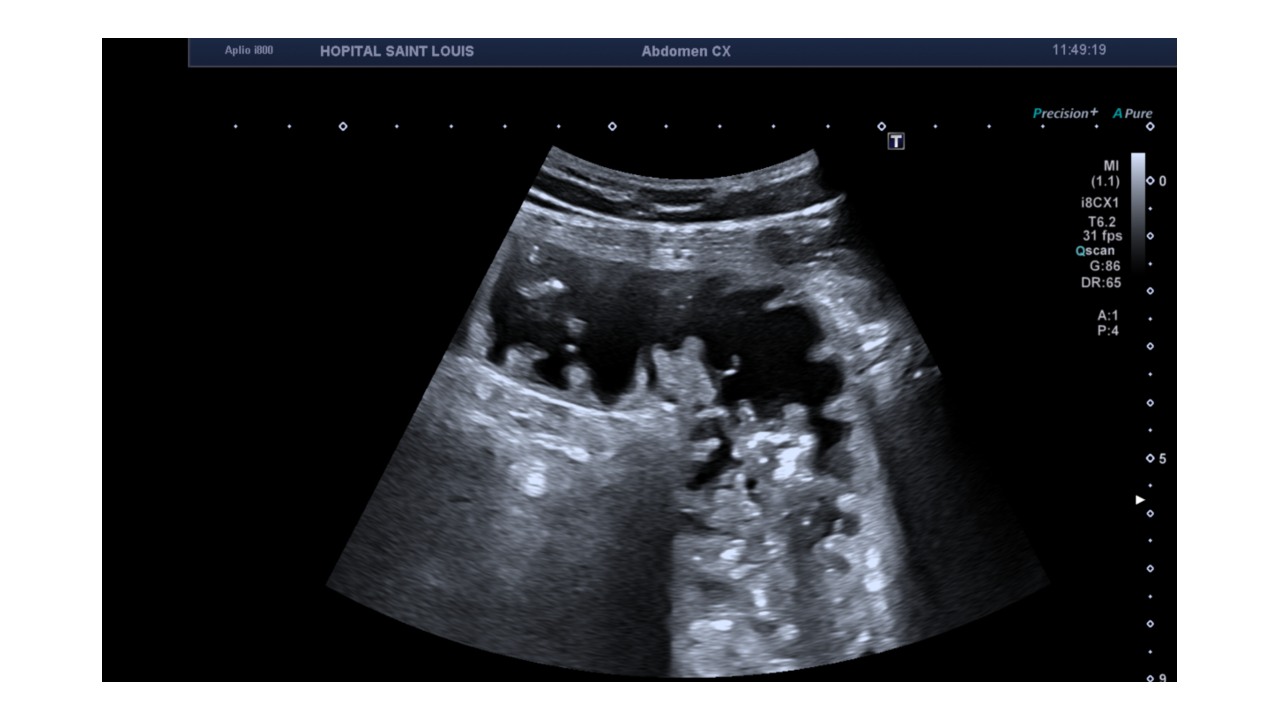

Voici le résumé du balayage réalisé par la manipulatrice en échographie.

Une distension d'une anse grêle mesurée à 37mm de diamètre antéro postérieur est détectée.

Le diamètre d’une anse grêle ne doit pas dépasser 25mm .

Un apéristaltisme est ausi observé.

Le patient est alors adressé au scanner pour compléter l’examen.

Après la réalisation du scanner, le patient se retrouve hospitalisé pour un syndrome occlusif .